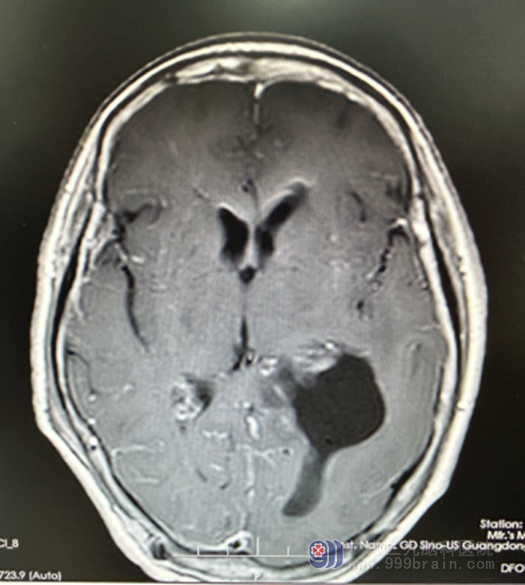

七月中旬,来自广东省湛江市的张女士,主诉近半年来无明显诱因出现记忆减退,当时未引起重视,近2个月来又出现言语迟缓,伴有四肢无力,但无明显恶心呕吐、四肢抽搐等不适,曾到当地医院就诊,查头颅MR示“左侧脑室三角区占位性病变,考虑脑膜瘤”,患者及其家属为进一步检查及治疗遂来我院就诊,我院欧阳辉教授将其收入神经外十科住院。入院后完善相关检查,3.0TMR结果提示:1..左侧侧脑室、三角区占位性病变,考虑脑膜瘤

检查意见:左侧侧脑室三角区病变血供丰富。

欧阳辉教授带领外十科团队,精心设计手术方案,对病人家属耐心讲解手术的建议和风险,家属接受了手术的治疗。7月25日在全麻下行“神经内镜下经对侧纵裂-大脑镰-同侧楔前小叶入路左侧脑室三角区脑膜瘤切除术+硬脑膜修补术+颅骨成形术”,术后很成功。